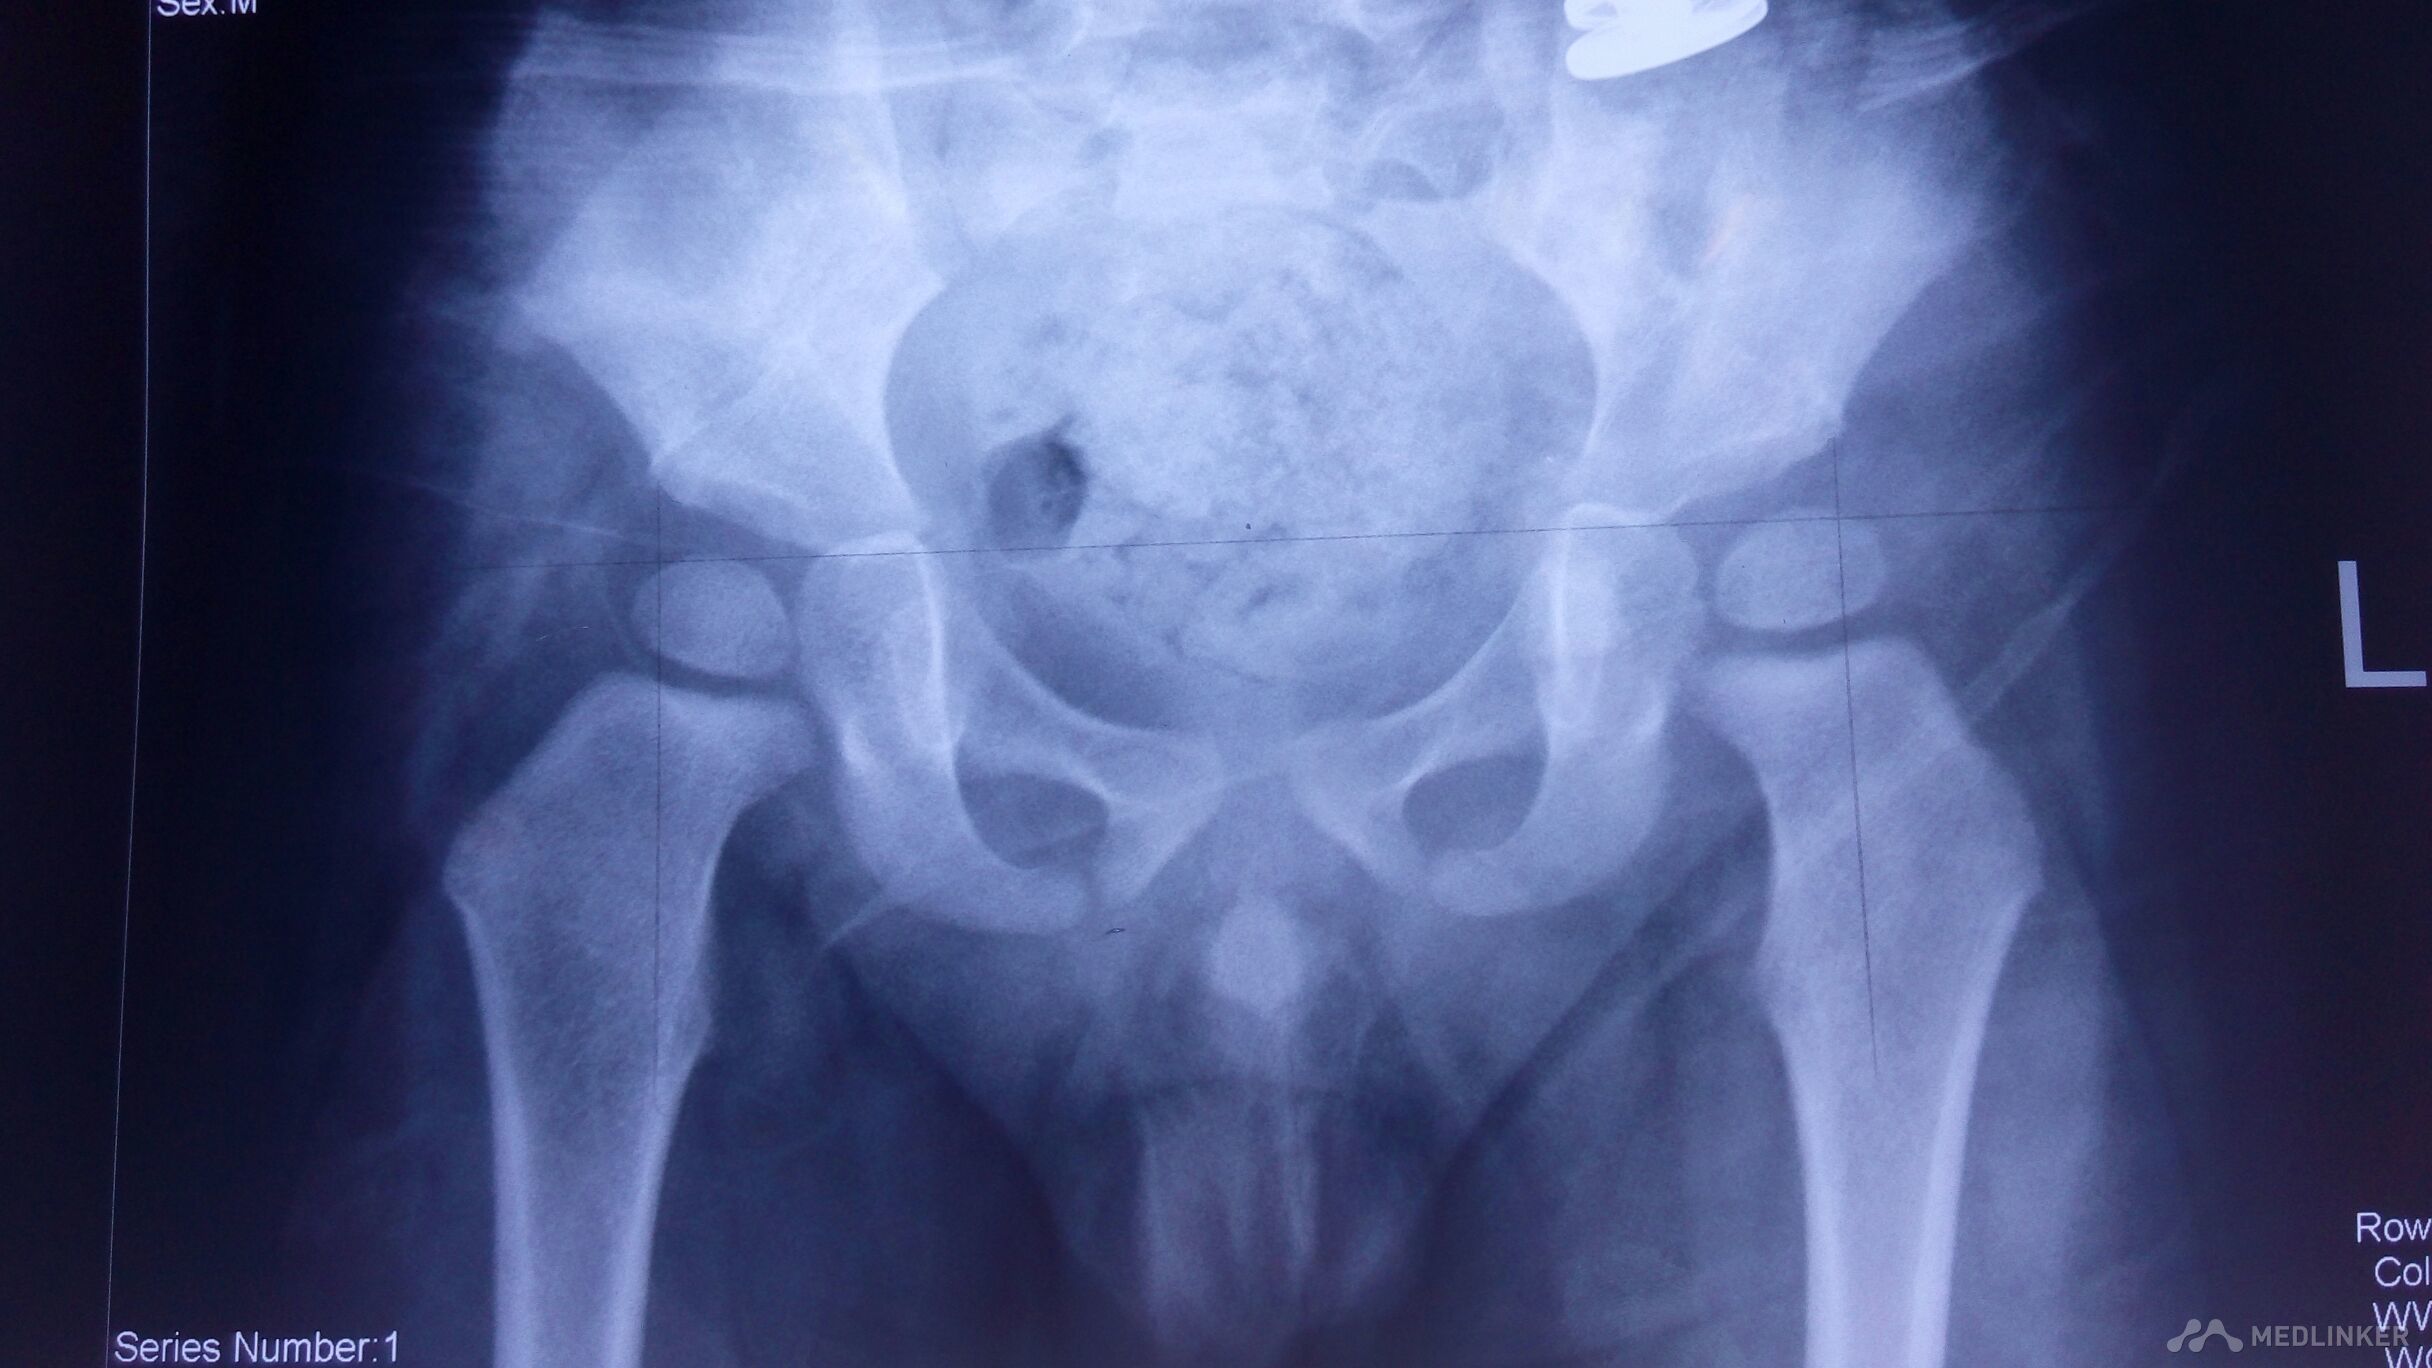

小儿先天性髋关节脱位的X线表现如何确诊?

先天性髋关节脱位